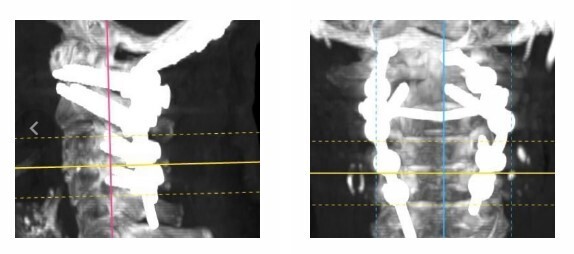

По их словам, остеопороз у пациентки не позволял надеяться на удачное сживление позвоночника с минимальным вмешательством. Поэтому женщине была проведена двухэтапная операция. На первом этапе были вправлены вывихнутые позвонки, ствол головного мозга и спинной мозг освободили от компрессии. На втором этапе были вживлены титановые конструкции. В ходе операции титановыми системами было зафиксировано правильное положение головы по отношению к позвоночнику и предотвращено повреждение спинного и головного мозга.

Операция прошла успешно, уже на следующий день женщина была в состоянии привстать, а через 12 дней при выписке из отделения могла свободно ходить. Сейчас пациентка проходит дальнейшую реабилитацию по месту жительства.